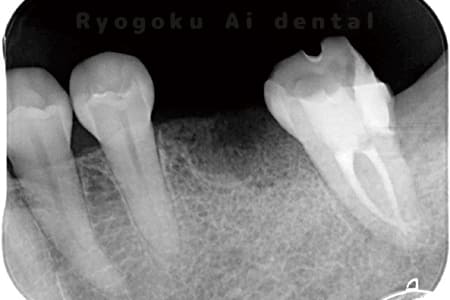

Case03

- 原因

- 急性化膿性根尖性歯周炎

- 治療期間

- 2ヶ月

- 治療内容

- マイクロエンド

- 治療費用

- 121,000円

黙っていても痛みが出るとのことで来院した患者様です。本治療は症状もあるため、抜髄治療をマイクロエンドで行いました。

<リスク・副作用>

術後は痛み、腫れ、痺れなどの副作用が生じる場合があります。症状が再発する可能性があります。